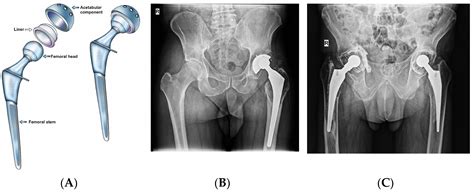

When you have a total hip replacement, the structural integrity of your hip joint is altered. The surgeon replaces the damaged bone and cartilage with artificial components, which need time to stabilize within the surrounding tissue. Following Total Hip Replacement Precautions is not just about avoiding immediate pain; it is about protecting the surgical site while the muscles and ligaments heal and adapt to the new mechanics of the joint.

If you fail to follow these guidelines, you risk putting undue stress on the prosthetic components, which could lead to dislocation or premature wear. Most surgeons will provide a list of "do's and don'ts" that are tailored to your specific surgical approach—whether it was posterior (back of the hip) or anterior (front of the hip). Understanding these rules will empower you to navigate your daily activities with confidence and safety.